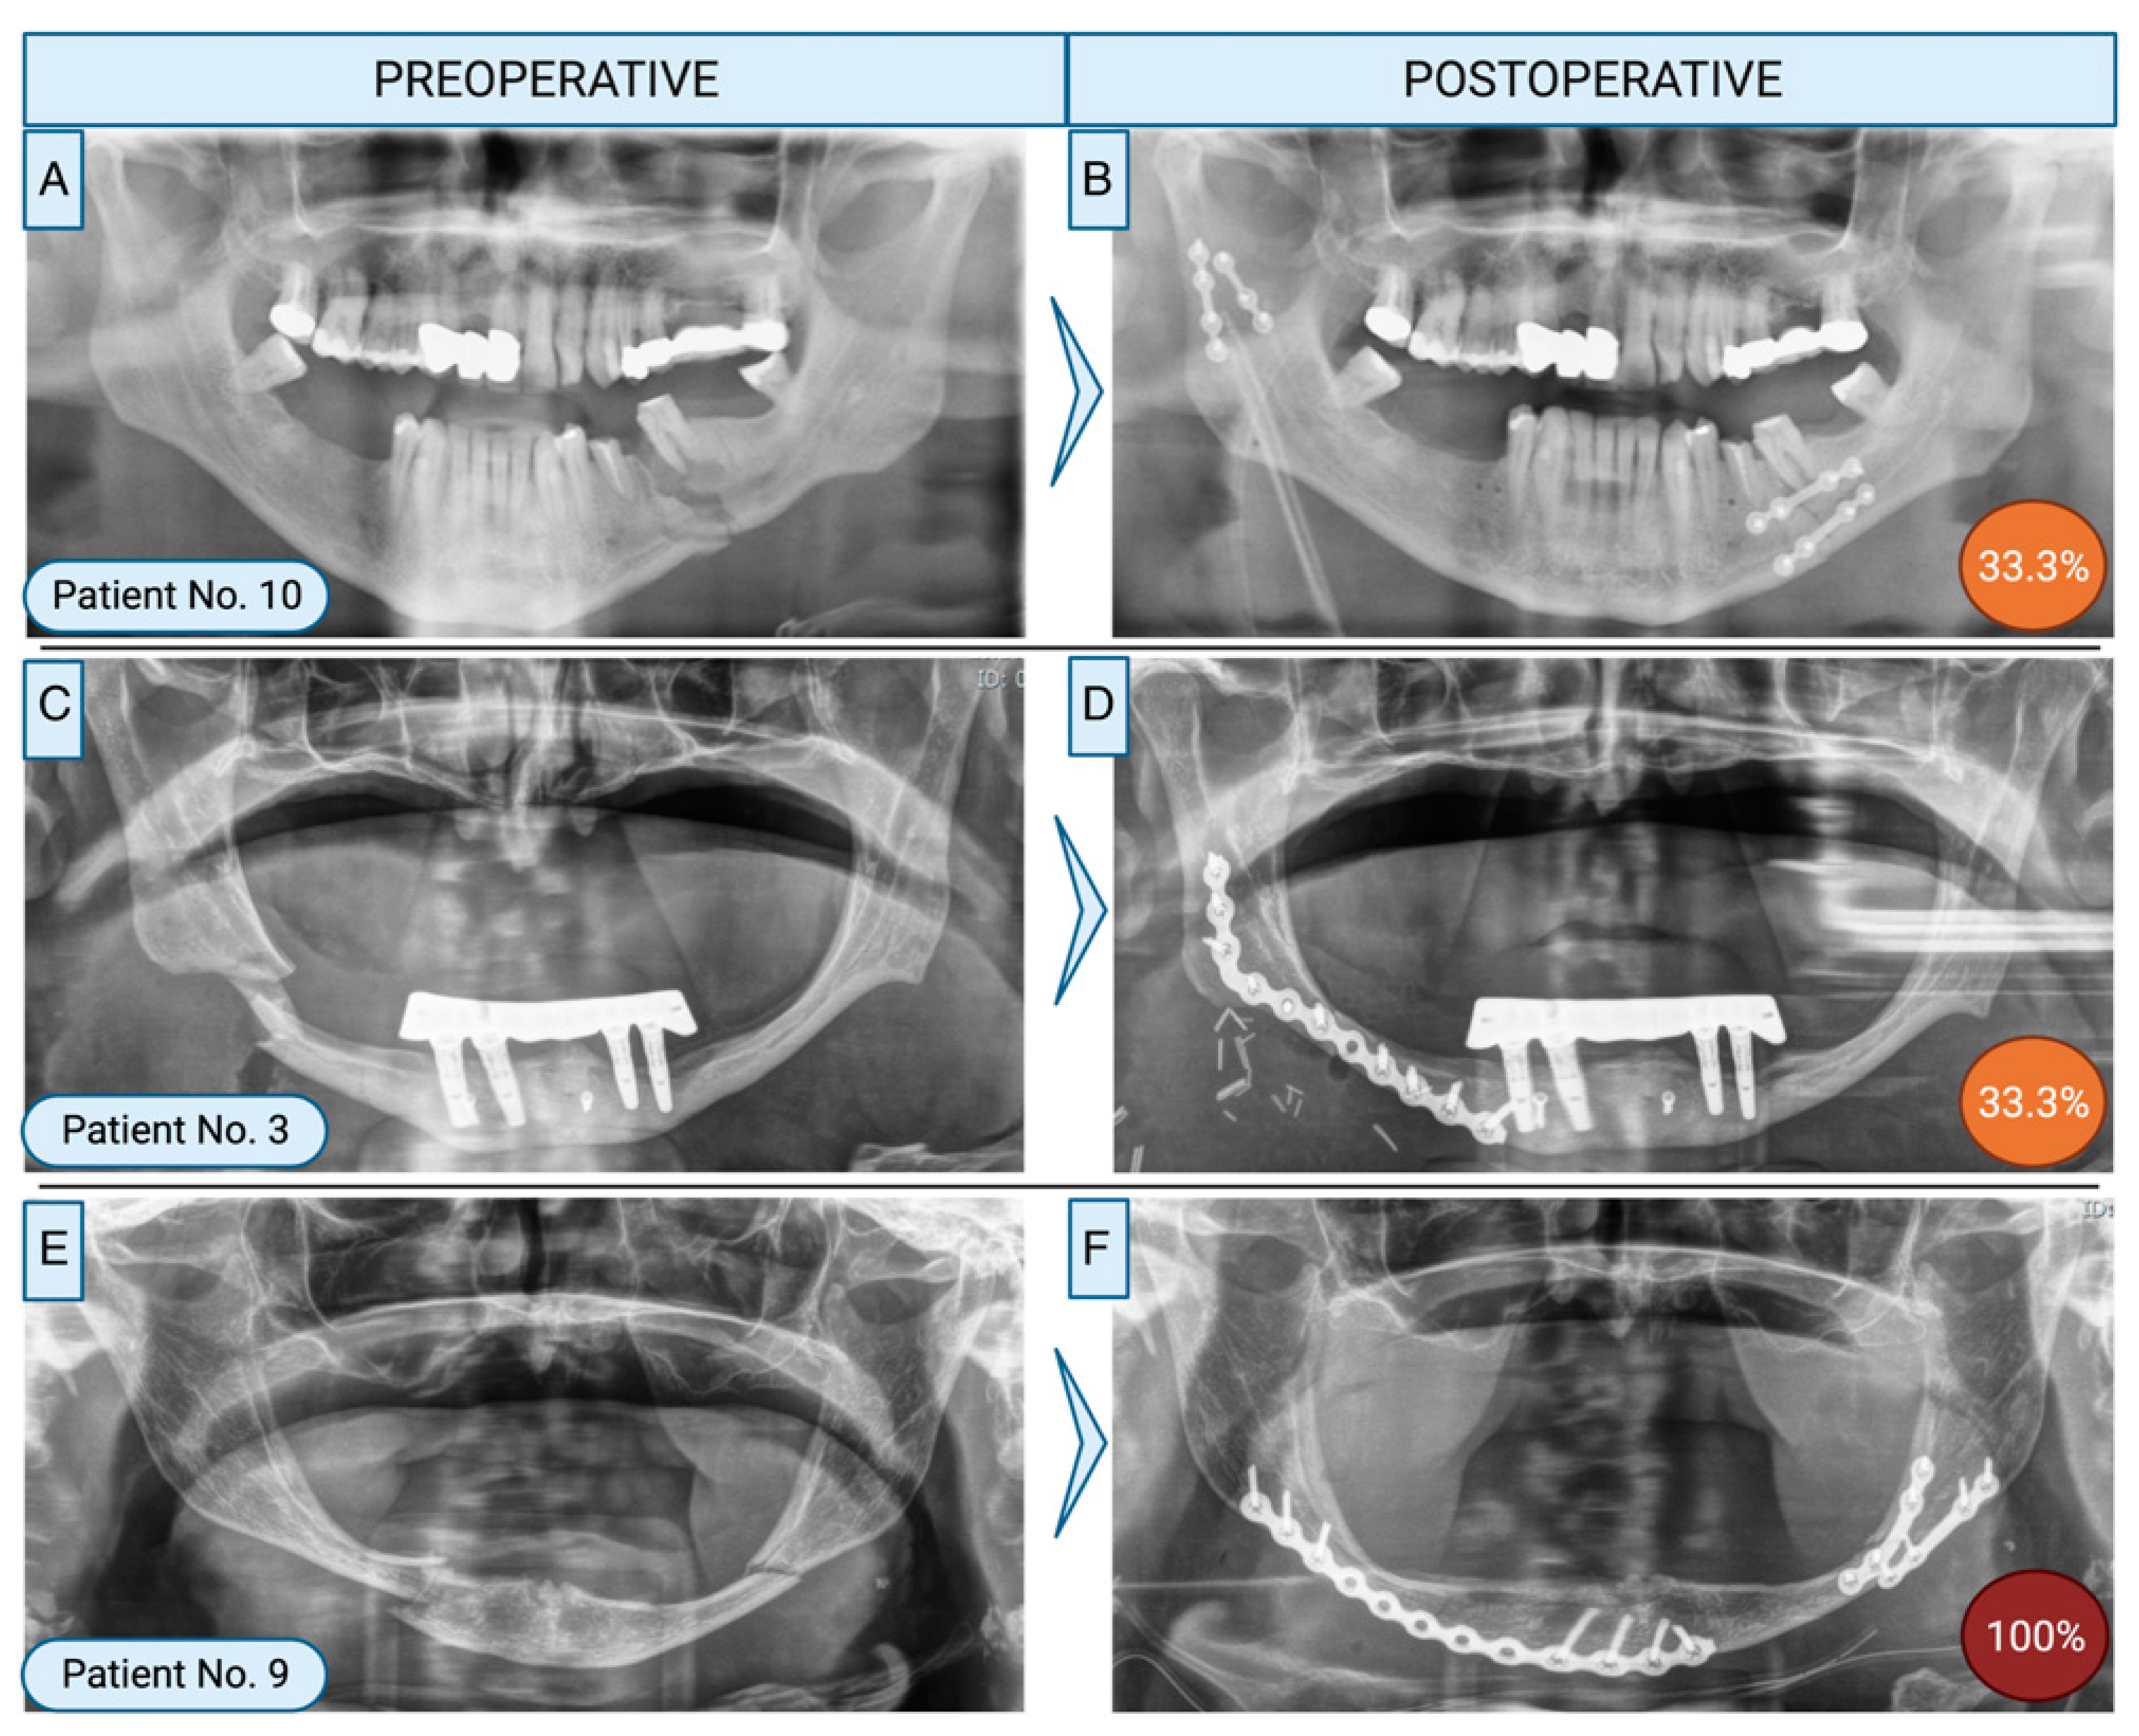

Figure 1. Examples of different insufficient fracture treatments in panoramic radiographs. A: Initial fracture showing a left-sided corpus and right-sided ramus fracture in a 48-year-old male patient without risk factors. B: The fracture was treated using miniplates. 33.3% of specialists rated the treatment as insufficient (orange). C: 59-year-old male patient with a right-sided corpus fracture in an atrophic mandible. D: The fracture was treated using a reconstruction plate. 33.3% of specialists rated the performed treatment as insufficient (orange). E: 88-year-old female patient with a bilateral corpus fracture in an atrophic mandible. F: Osteosynthesis was performed using 1 reconstruction plate and 2 miniplates. All specialists rated the treatment as insufficient (red). Created with Biorender.com.